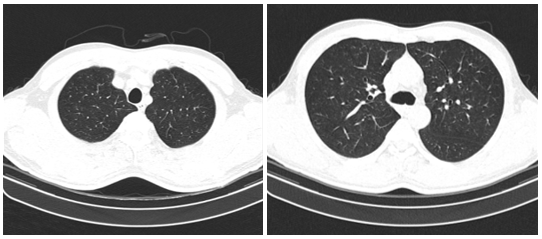

Hình 2: Hình ảnh cắt lớp vi tính lồng ngực chưa phát hiện tổn thương nghi ngờ thứ phát

- Cắt lớp vi tính lồng ngực: